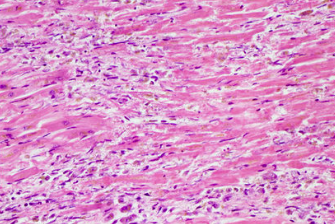

When would this histopatholigcal slide from an MI likely to have occurred

Less than 1 day

Less than 7 days

1-3 week

3-6 weeks scarring occurring